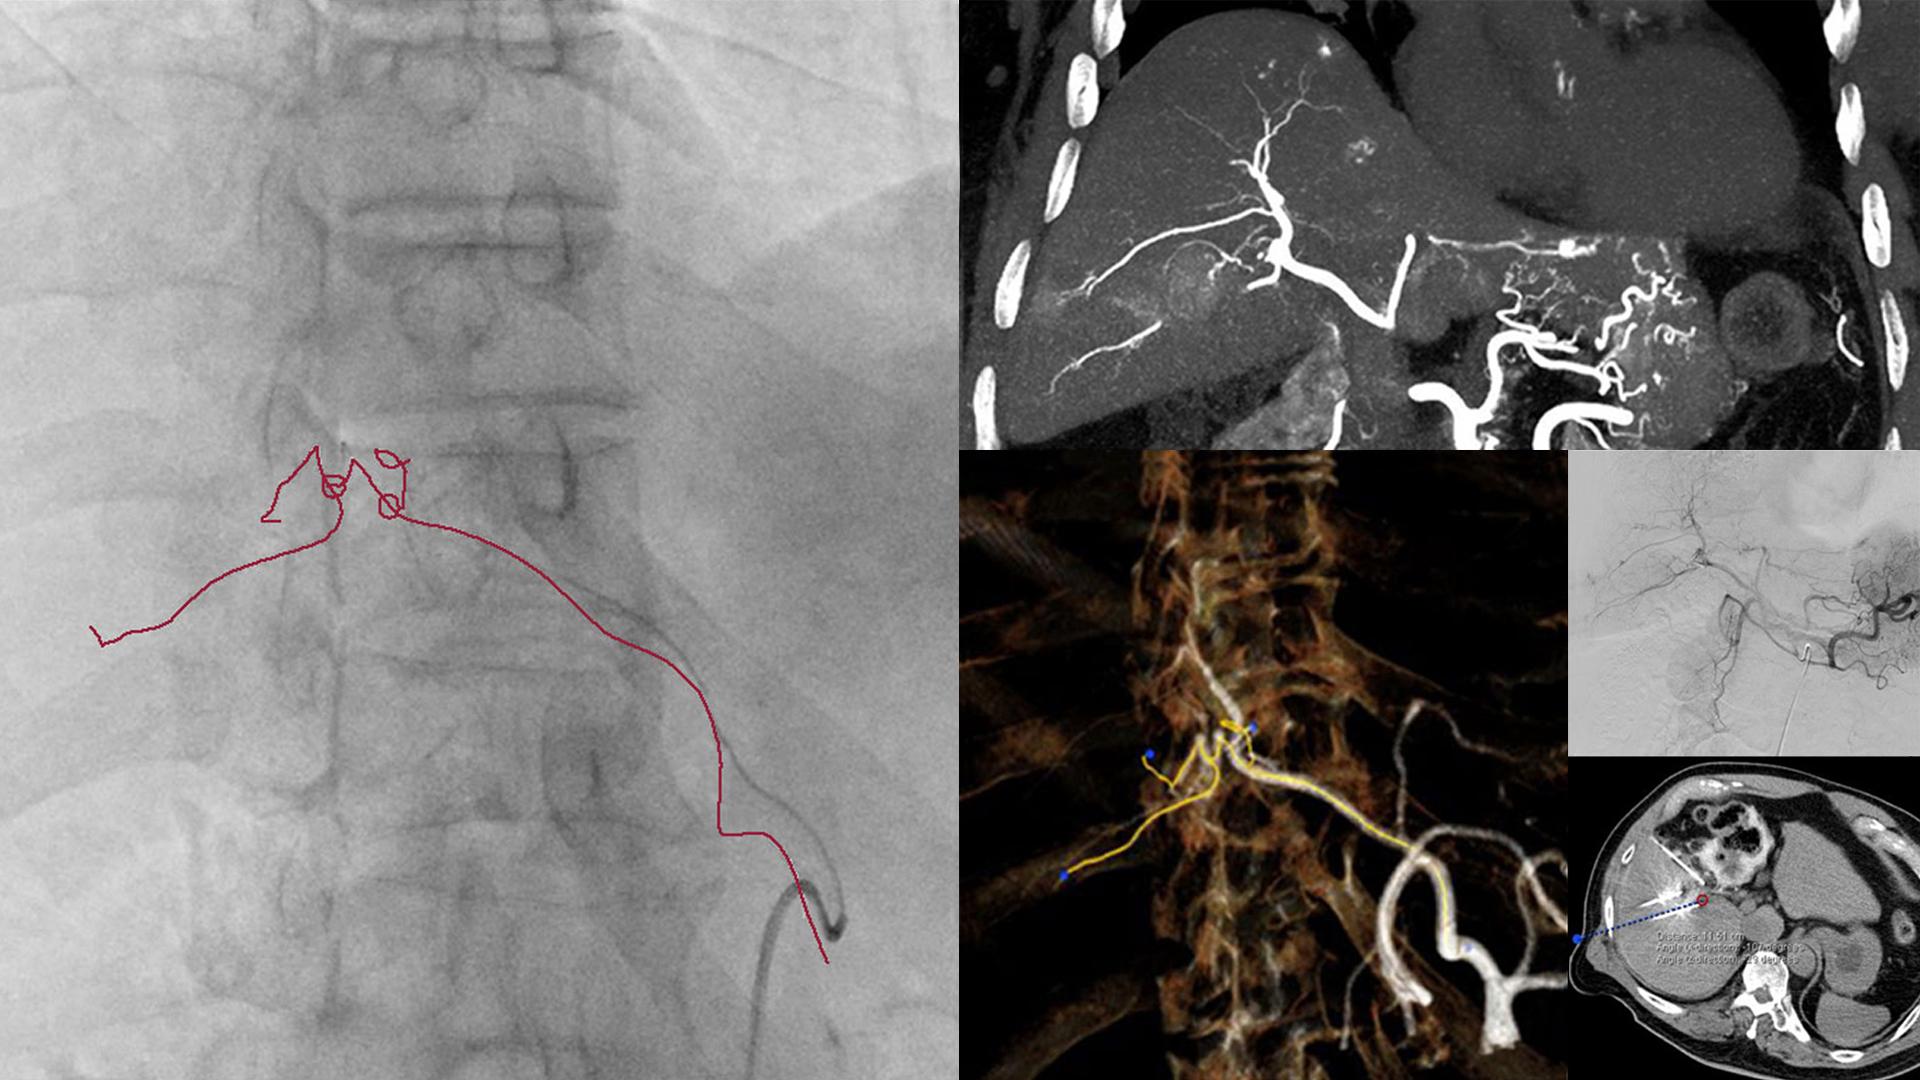

In this multi-modality suite, it’s easier to reach targets and — should complications arise — detect them and react promptly. With this safety net, you’re free to expand the scope of IR-based therapy in growth areas such as palliative oncology and acute care.

• Treat bone metastasis in the pelvis or spine with ablation, bone cement and screw fixation

• For blunt poly trauma, locate bleeding with the CT and stabilize it under angio guidance

• Faster acute stroke treatment with CT diagnosis and angio-guided clot retrieval in one room